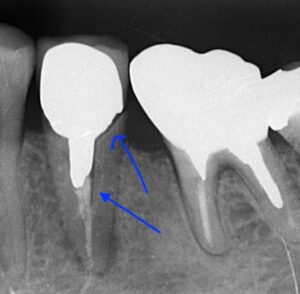

画像のレントゲンは矢印の部分が歯が折れており抜歯適応となります。

抜歯後インプラントを埋入しましたが骨が足りずネジが

5年後のレントゲン写真です。特に変化はなく

良好です。